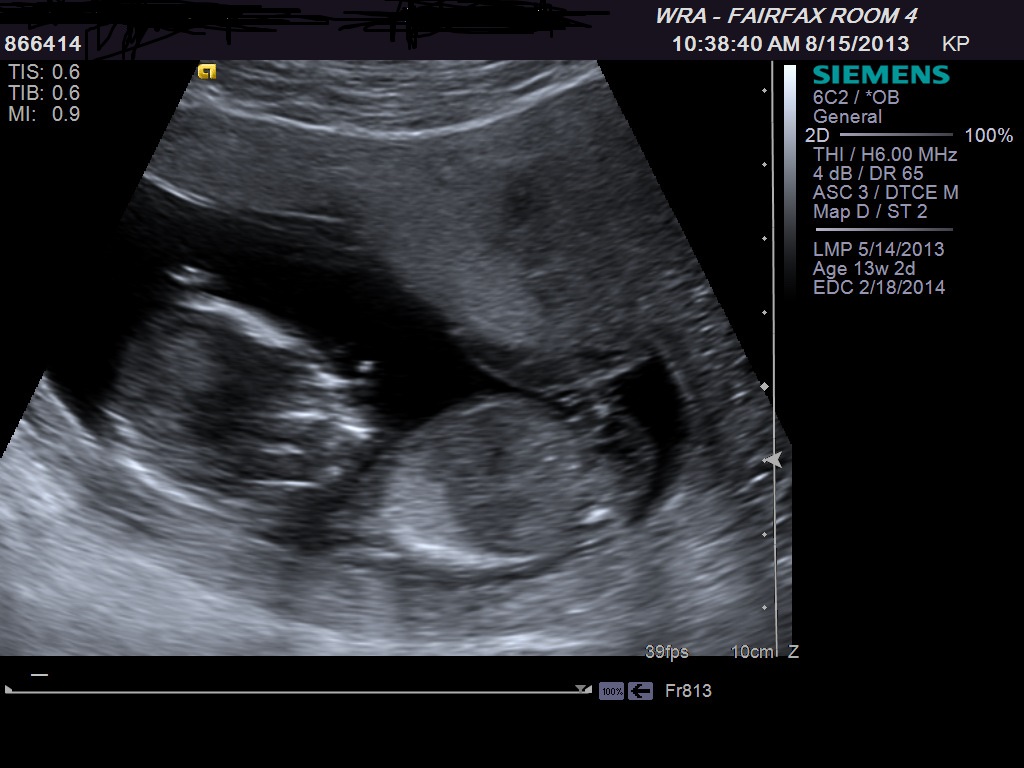

How far along are you? Thinking maybe girl...